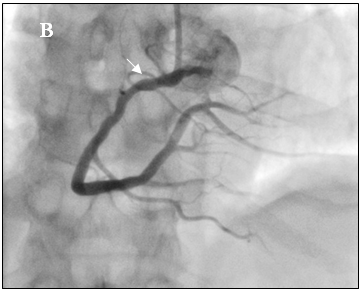

Bệnh nhân được chẩn đoán nhồi máu cơ tim cấp vùng hoành giờ thứ 2, Block A-V độ 3, có chỉ định chụp mạch vành cấp cứu. Bệnh nhân được kích nhịp bằng Atropin, Dopamin và truyền dịch chống choáng trên đường chuyển đến phòng thông tim. Kết quả chụp mạch vành cho thấy hẹp 90% ở đoạn xa RCAI (hình 6a), tuy nhiên khi chuyển sang góc chụp kế tiếp chúng tôi phát hiện thêm một chổ hẹp thứ hai rất nặng ở đoạn gần RCAI tại vị trí sát ngay đầu ống thông can thiệp (hình 6b). Nghi ngờ tổn thương do co thắt nên chúng tôi bơm 200µg Nitroglycerin vào RCA và chụp lại sau 2 phút. Kết quả chổ hẹp nặng ngay sát đầu ống thông can thiệp đã hoàn toàn biến mất (hình 7b), chổ hẹp đầu tiên ở đoạn xa RCAI chỉ còn 30% (hình 7a). Như vậy, nhồi máu cơ tim vùng hoành là do co thắt RCA tại vị trí mãng xơ vữa.

Hình 7: (A) Hẹp 30% đoạn xa RCAI

(B) Không còn chỗ hẹp gần đầu Guiding